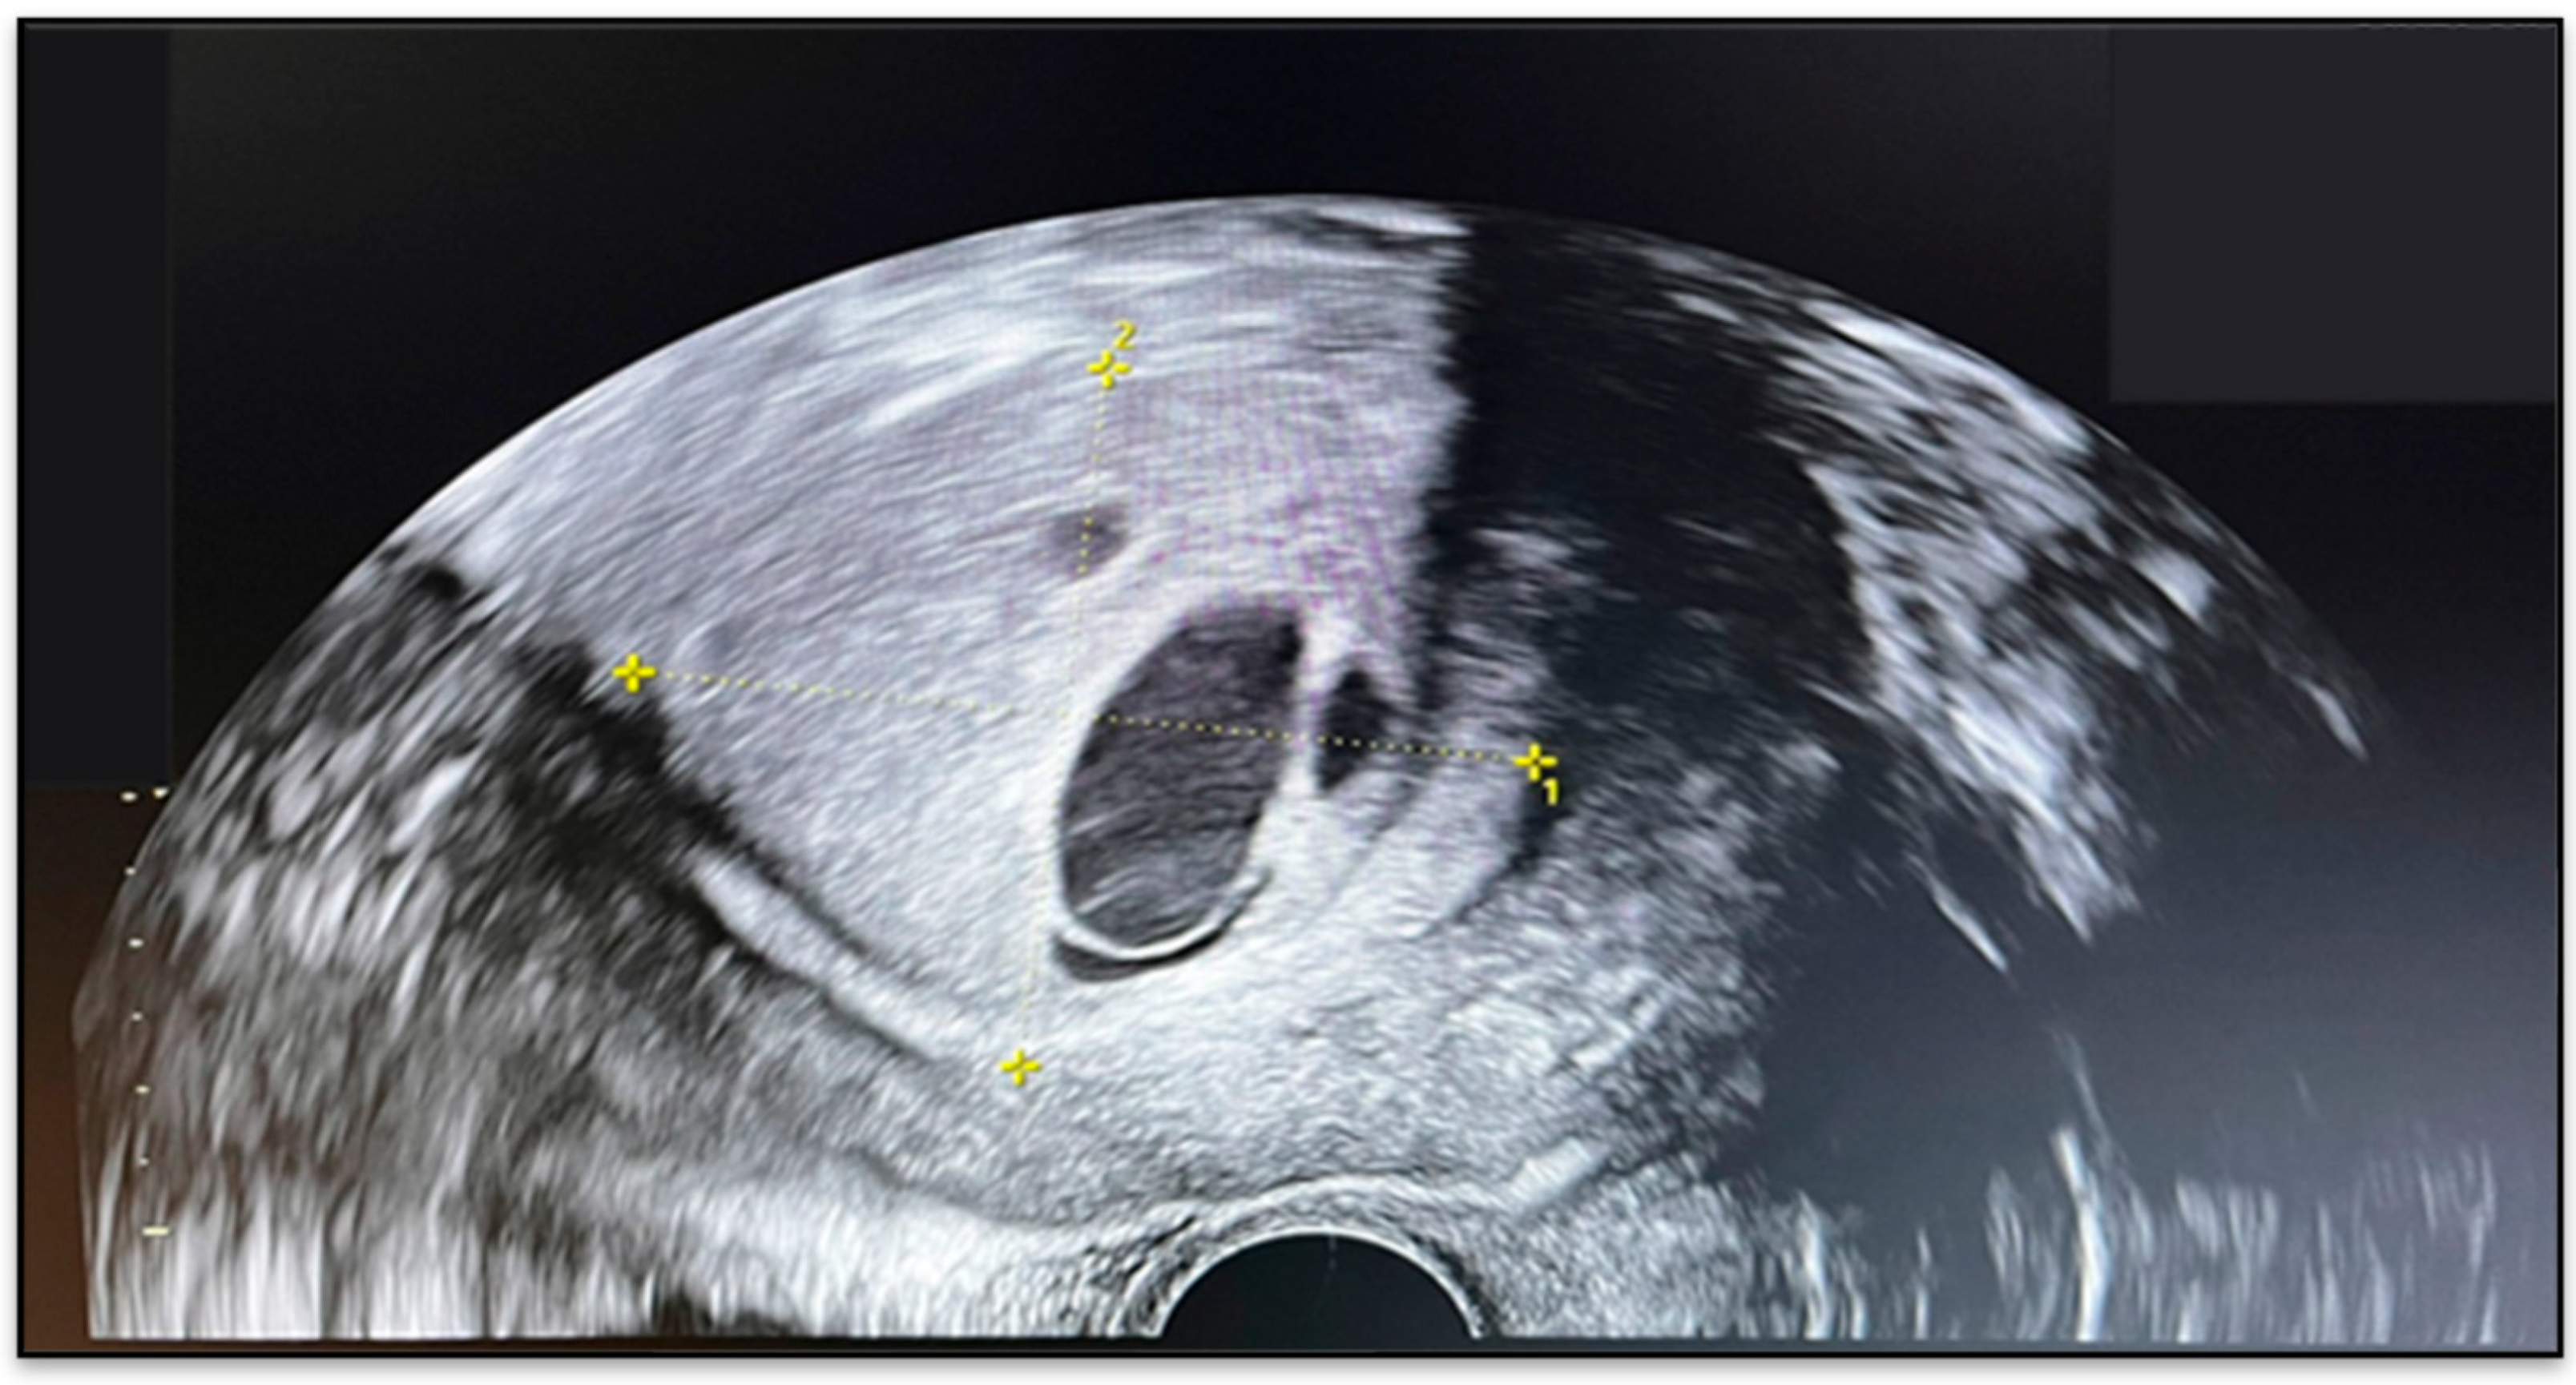

2.2. Imaging Findings

3.4. Imaging and Clinical Presentation